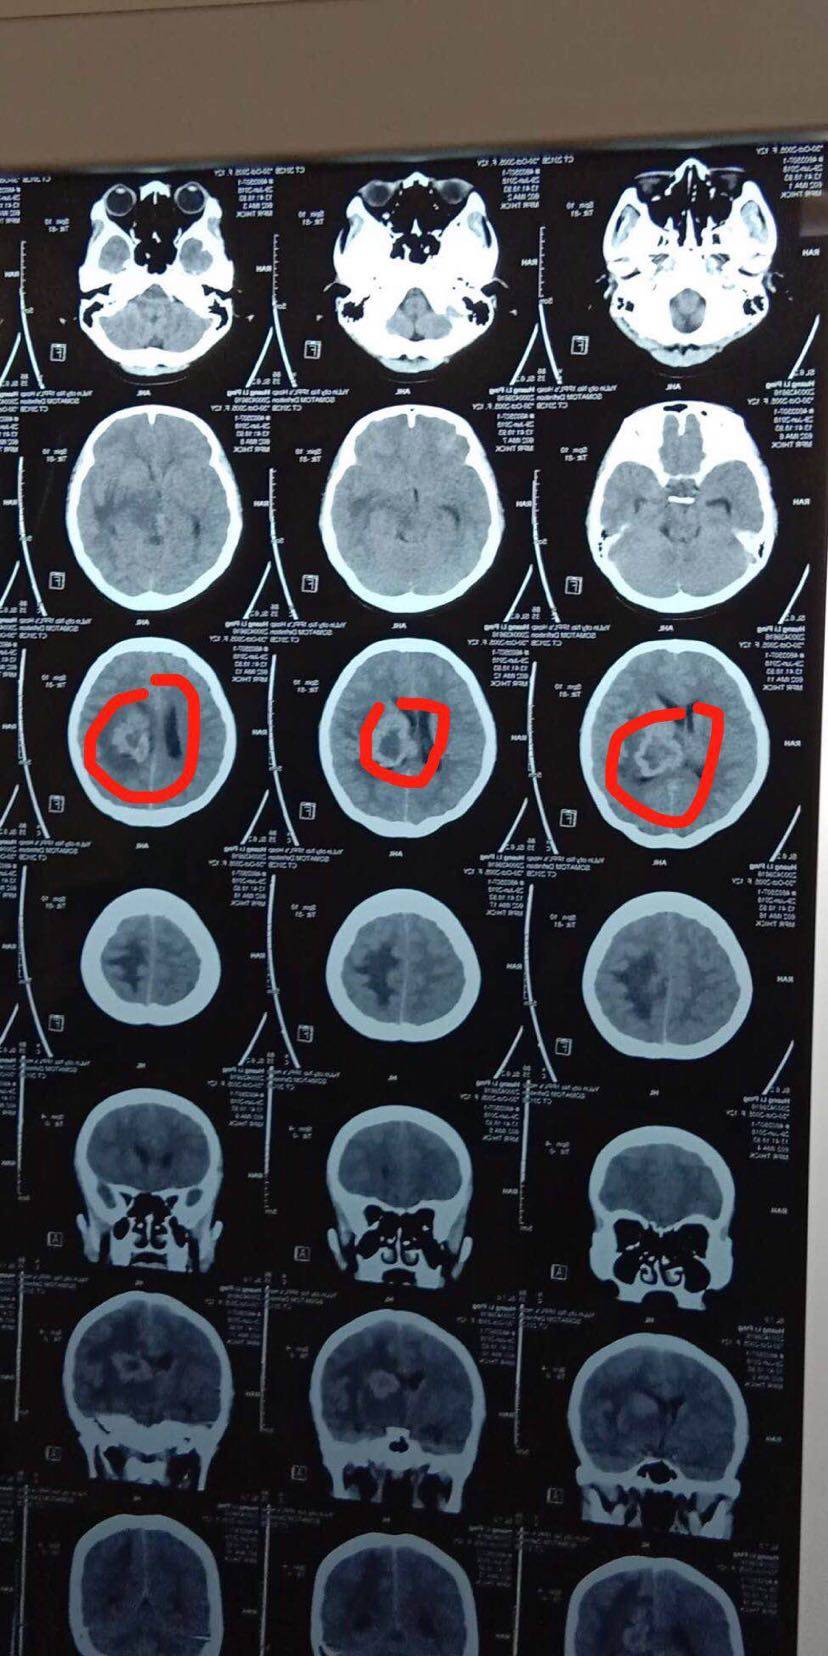

第二步:用放射性碘125粒子,通过三维立体成像技术(3D影像),铺助3D建模精准植入到肿瘤内部,在内部持续杀死肿瘤,不伤害正常细胞。

把河里的鱼捞完了是不是就可以万事大吉了呢?不是!河里的鱼卵还在,也就是休眠期的肿瘤细胞还在,不处理它,等到合适的时候,它一定会重新长出来。所以采用放射性碘125粒子植入,小型的核导弹精准打击彻底摧毁目标范围内所有的一切生物。